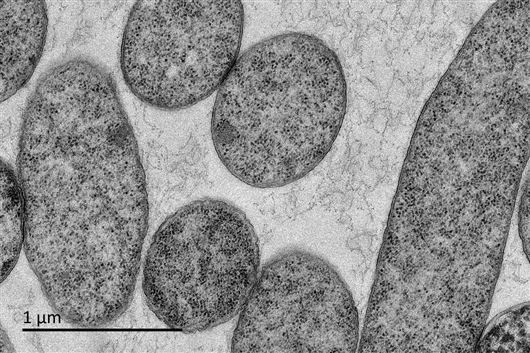

经过AI挖掘到的抗菌肽分子(10倍最低抑菌浓度)处理后的大肠杆菌。透射电镜下可明显观察到大肠杆菌细胞内容物的泄露及细胞膜或细胞壁的破坏。论文作者供图

为了解其作用机理,研究者通过对11种抗菌肽进行测试,确定了其中部分肽的作用位点分别为细胞膜和细胞壁。“如果用电子显微镜观察,可以看到和抗菌肽共培养的大肠杆菌细胞膜明显破裂。这样细胞内容物外流,耐药微生物就被杀死了。”陈义华向记者解释。

透射电镜下观察抗菌肽处理的大肠杆菌超薄切片(10倍最低抑菌浓度,放大倍数8000),可明显观察到细胞结构的进一步破坏和内容物泄露。 论文作者供图